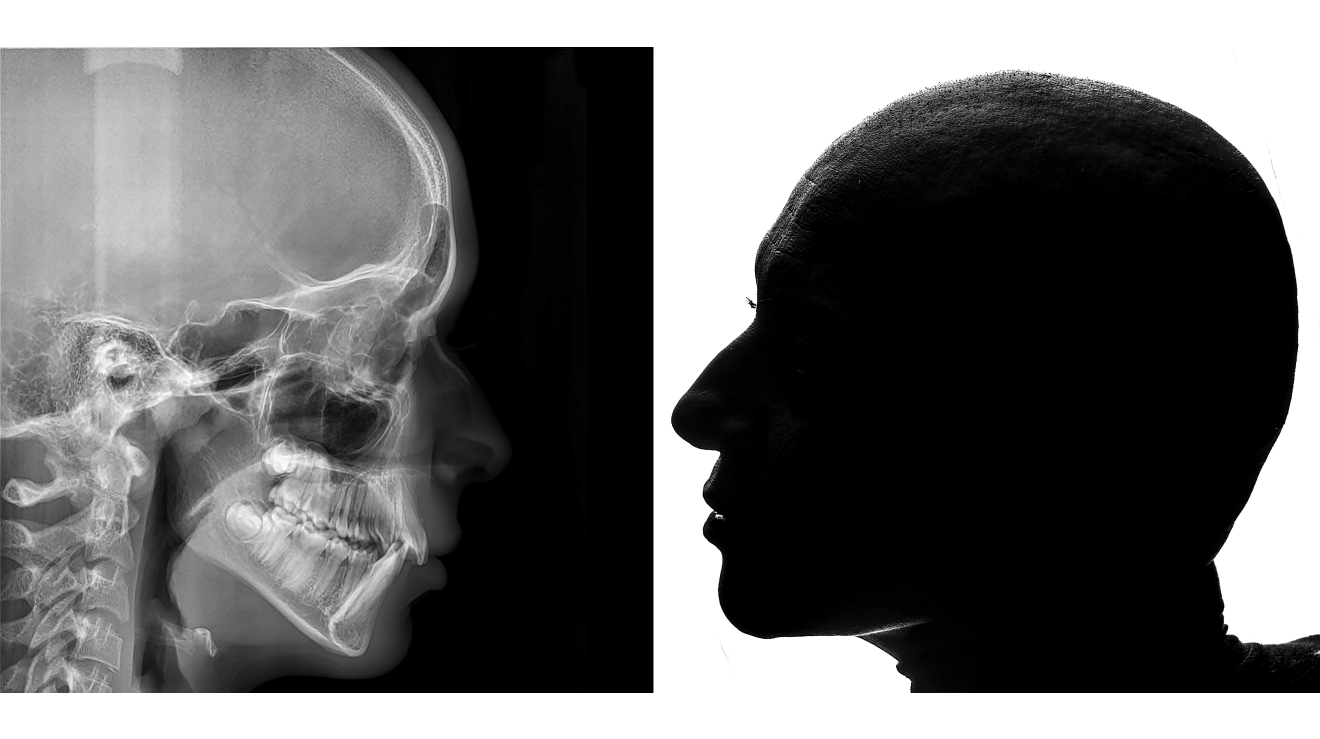

Η εικόνα παρουσιάζει δύο αντιδιαμετρικά αποτυπώματα ανθρώπινης υπόστασης σε μαύρο και άσπρο, που συμβολίζουν το κρίσιμο σημείο αλλαγής και ανανέωσης. Στην αριστερή πλευρά, ένα ακτινογραφικό προφίλ ανθρώπινου κρανίου και σπονδυλικής στήλης, που αντιπροσωπεύει το παρελθόν, το σκιώδες και το παγωμένο. Στην δεξιά πλευρά, ένα σκούρο, επιβλητικό προφίλ ανθρώπου που κοιτάζει μπροστά, συμβολίζοντας το νέο ξεκίνημα, την αυτογνωσία και την εσωτερική δύναμη. Η αντίθεση αυτή αντικατοπτρίζει την απόφαση να ζήσει ξανά, με μια νέα αντίληψη και εσωτερική αναγέννηση, σε μια στιγμή που σηματοδοτεί το turning point της ζωής.